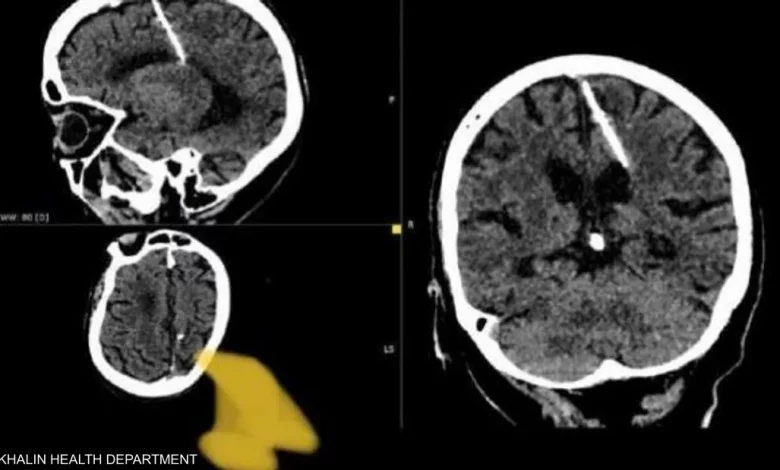

عثر أطباء خلال فحص بالتصوير المقطعي على إبرة بطول ثلاثة سنتيمترات موجودة منذ ثمانين عاماً داخل دماغ امرأة مسنّة في أقصى الشرق الروسي.

ويعتقد الأطباء أن المرأة تعرضت لمحاولة قتل فاشلة نفذها والداها خلال طفولتها، وقالوا إنهم لن يحاولوا إزالة الإبرة خشية أن يفاقم ذلك حالتها.

وأضافت أن والديها قررا على الأرجح التخلص من طفلتهما خلال الحرب العالمية الثانية، لأنها كانت تعيش مع إبرة يبلغ طولها ثلاثة سنتيمترات “منذ ولادتها”.